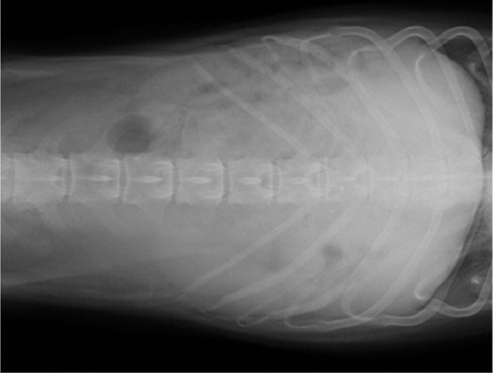

【画像診断】~ダックスフンド、雄10歳、グレート3の椎間板ヘルニア~

▲ダックスフンドのCT像、病変の部位は胸椎T11-12、白い部分(武蔵野動物CTセンターにて)

はい、たいへん有効です。その椎間板ヘルニアの起こっている部位や、左右どちらに起こっているか、その他の異常(合併症等)があるかもこの検査で調べます。脊椎の診断はMRI検査が最も理想的な検査法ですが、撮影時間や費用、設備の有無等に制約があるます。より実用的な検査としてはCTも良い検査法になりますが約15%でその部位に石灰化が起こってないとわらない場合がありますが、そんな場合は造影をすれば判定できます。MRIの場合、椎間板の変性はT2強調像、矢状断面像で最も良く観察、でき脊髄腫瘍、椎体腫瘍等、脊髄髄内の検出にも理想的な検査です。多くの腫瘍はT1強調像では脊髄と比較すると等信号から低信号にT2強調像では高信号となります。